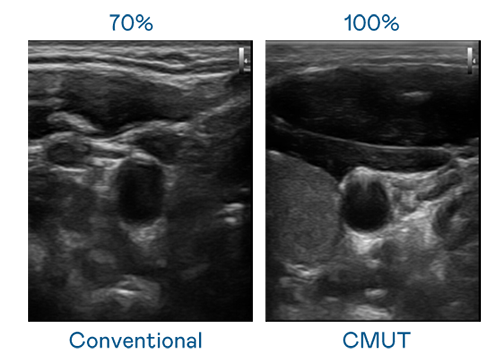

CMUT 技术是一种用电容式微机电元件来产生超音波讯号的技术。与传统 PZT 压电式技术相比,CMUT 频宽增加 30%,更宽频的超音波讯号让影像解析度大幅提升,是实现高影像品质医疗超音波扫描、促进精准医疗发展的关键技术。

超音波影像的解析度高低,首先取决于探头能发出的讯号频宽。英国上市公司365 CMUT 可提供高清晰的超音波讯号,提供高频宽、高灵敏度、影像纹理细节更高的超音波影像,协助医护人员缩短影像判读时间及利用精准的医疗影像进行诊断。